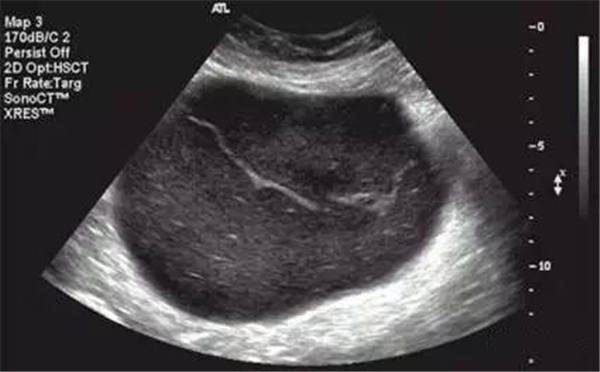

声像图特点:1、子宫增大边界不规则。2、肌瘤结节呈低回声、等回声或强回声。等回声周边可有低回声晕呈假包膜。3、子宫内膜移位或变形。4、膀胱变形,易引起尿贮留。5、肌瘤结节周围呈环状及半环状血流。阻力指数0.6±0.1。

声像图特征:1、子宫均匀性增大,边界规则。2、子宫内膜线前移。3、子宫内回声不均匀,低回声、强回声区,无包膜。4、子宫大小、内部回声月经前后常有变化。5、肿块周围无环状或半环状血流,阻力指数约0.6。